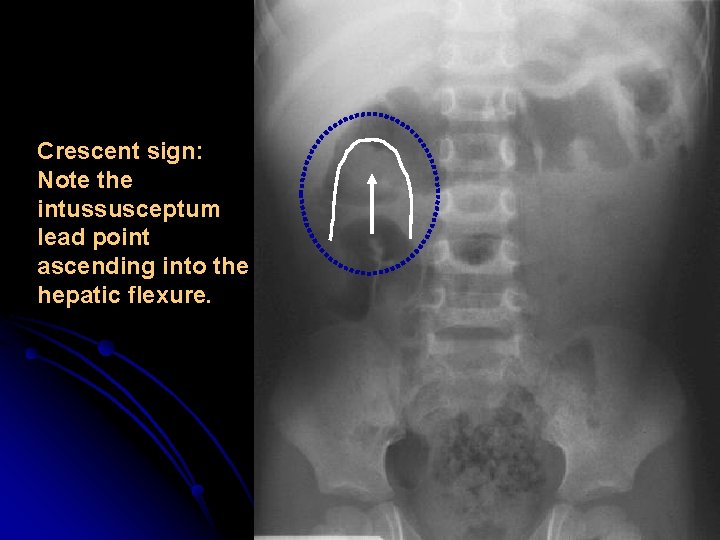

Diagnosis & Treatment l Abdominal plain films: l Crescent sign l Target sign l Ultrasonography: l Bull’s eye sign l Coiled spring sing l Target sign l CT scan (3 -1)

Crescent sign: Note the intussusceptum lead point ascending into the hepatic flexure.